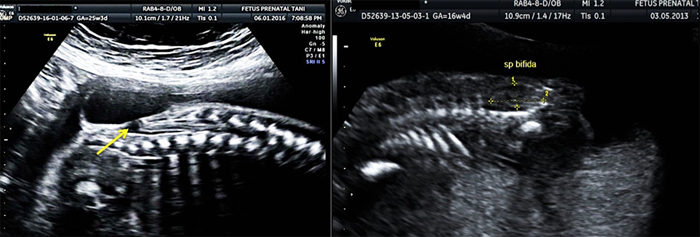

• Nörosonografi (beyin – omurga yapıları)

• Santral sinir sistemi (beyin - omurga – omurilik)

Nörosonografi

Fetal nörosonografi, beyin yapıları ve omurga - omurilik anatomisinin değerlendirilmesidir. Santral sinir sistemi yapılarının aksial – sagital ve koronal planlarda incelenmesidir. Bu incelemede: